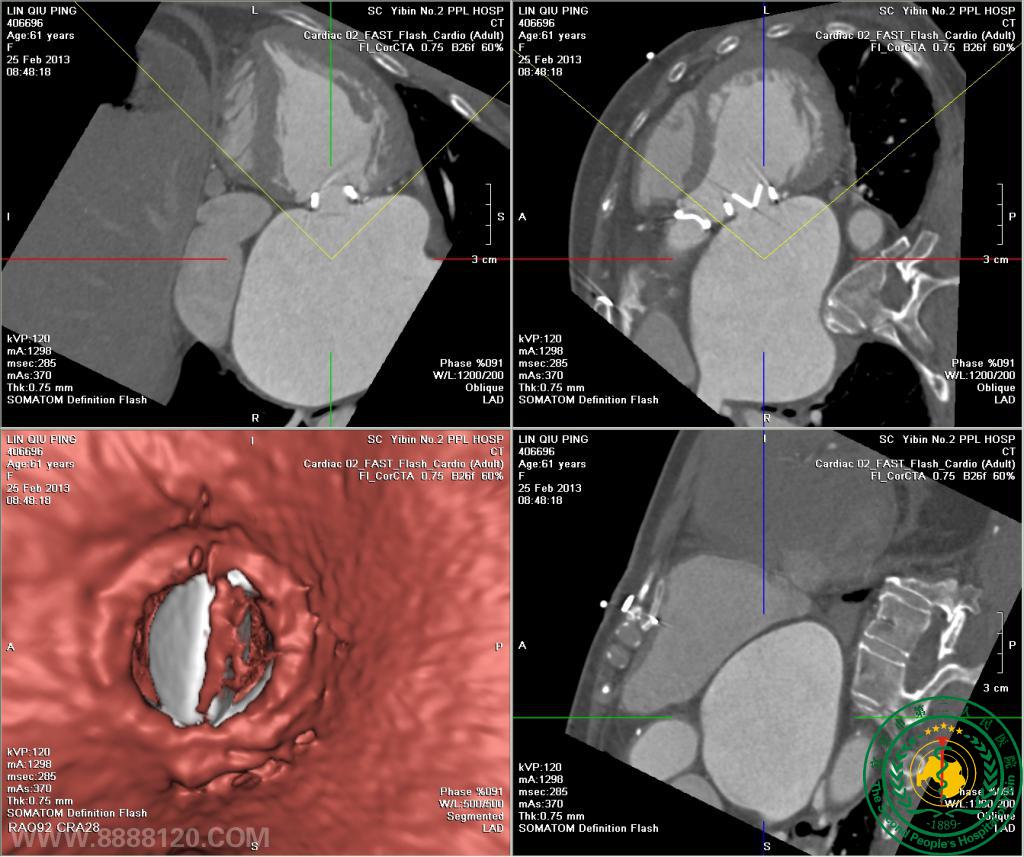

我院开展炫速双源CT对风心病的换瓣或成形术术前、术后评估技术

我院开展炫速双源CT对风心病的换瓣或成形术术前、术后评估技术3850

宜宾市第二人民医院 图文